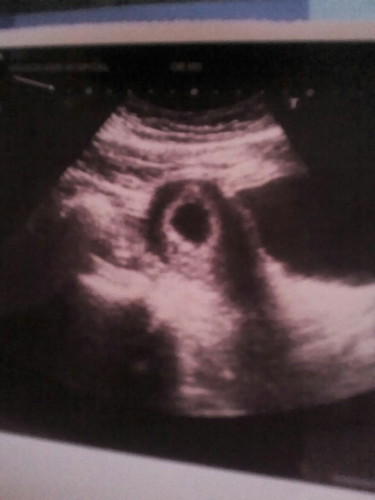

เราก็เป็นแบบในรูปคะ ตอน6วีค เห็นแต่ถุงตั้งครรภ์ ตอนนี้34 วีคแล้วคะ สัก9สัปดาห์ซาวใหม่ อย่าเครียดคะ ขอให้ซาวเจอน้องจ้า